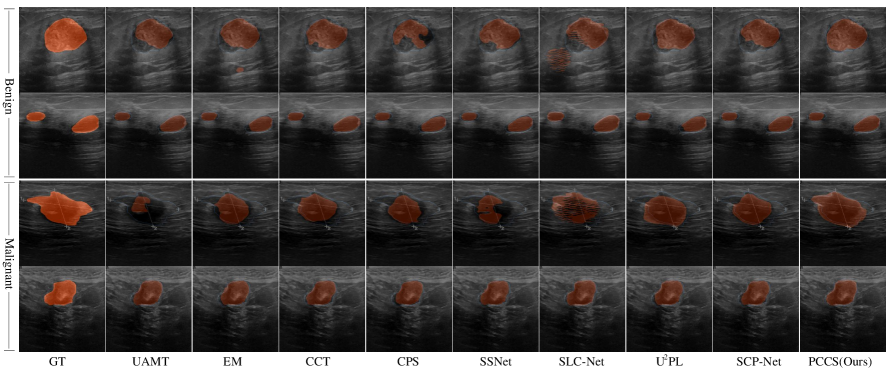

Results of Comparison on Visualization. Fig. 5 shows the visualization results of various methods applied to the BUSI dataset when using 20% annotated images and 80% unannotated images. A comparative analysis is conducted among nine methods: UAMT, EM, CCT, CPS, SSNet, SCL-Net, U2PL, SCP-Net, and PCCS. The leftmost column represents the Ground Truth (denoted as GT), providing a reference for comparison. The first row showcases the segmentation outcomes of benign tumors, while the second row demonstrates the segmentation results of malignant tumor. It is noticeable that benign tumor in breast ultrasound image typically displays relatively regular boundaries resembling ellipses, whereas malignant tumor in breast ultrasound image tend to exhibit irregular boundaries with sharp protrusions. Traditional semi-supervised methods often excel in learning features associated with benign tumors characterized by regular boundaries, yet struggle to accurately segment malignant tumors with irregular boundaries. In contrast, PCCS effectively constructs relationships among boundary prototypes, enabling the learning of more discriminative features. Consequently, the segmentation results produced by PCCS for malignant tumors demonstrate a closer alignment with the true boundaries of the Ground Truth, exhibiting fewer missing and unexpected regions.